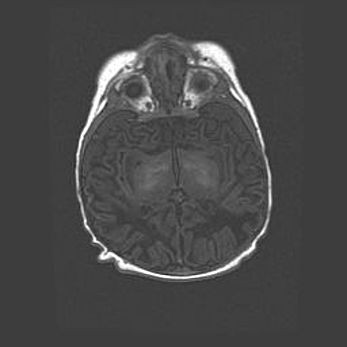

Подострая гематома правой гемисферы мозжечка.

Наружная гидроцефалия.

Возраст: 15 дней

Вес: 3100 г

Пол: женский

Окружность головы: 37 см

Срок гестации: 35-36 недель

При открытой наружной форме гидроцефалии у новорожденных расширяются и переполняются субарахноидные пространства.

Кровоизлияния в мозжечок имеют две клинико-анатомические формы: полушарные гематомы и кровоизлияния в червь.

К появлению этой патологии может привести: повреждения головного мозга, возникающие в результате асфиксии и гипоксии плода при беременности, или травмы во время родов. Редко гематома мозжечка может быть результатом первичной коагулопатии и сосудистой мальформации, диссеминированном внутрисосудистом свертывании, изоиммунной тромбоцитопении.